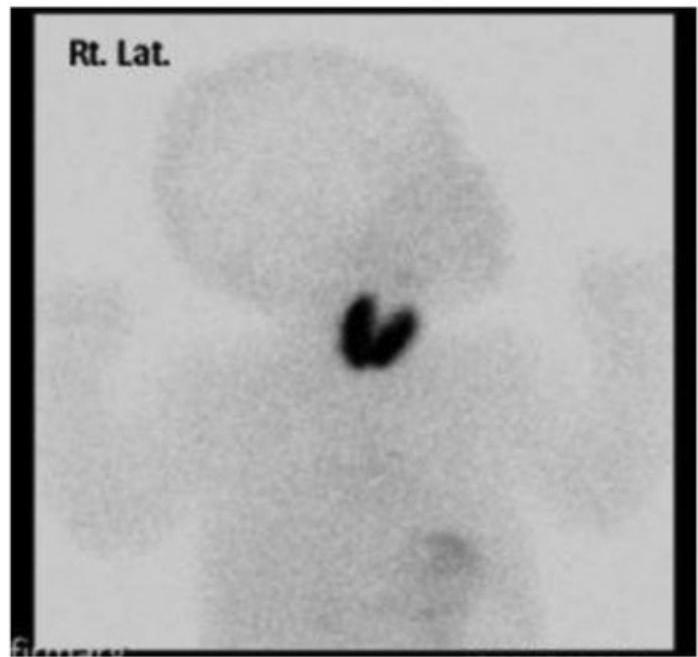

- Thyroid agenesis or hypoplasia

- Ectopic thyroid gland